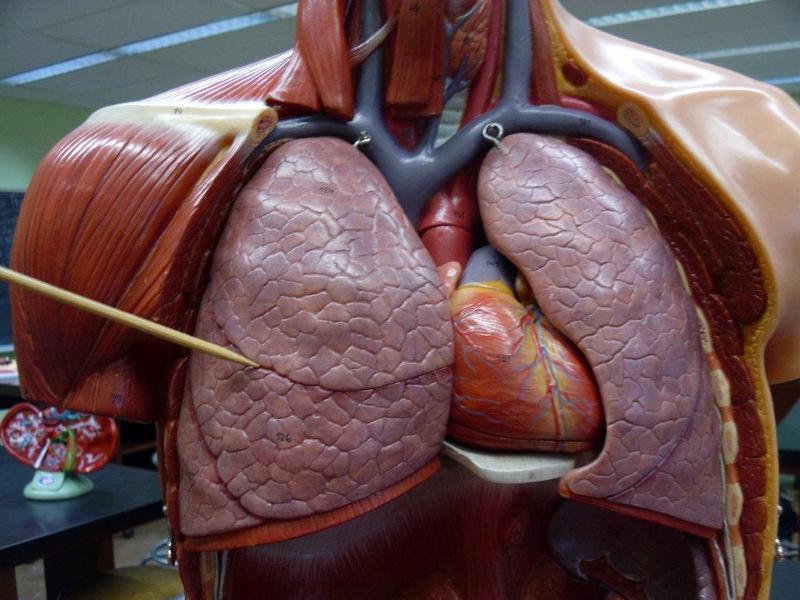

Alveolus/alveoli

Bronchioles

Horizontal fissure (of right lung)

Internal/external intercostal muscle

Left/right oblique fissue (of lung)

Left/right primary bronchus/bronchi

left/right pulmonary artery/vein

Pleural cavity

Pleural membrane

Secondary bronchi

Upper/middle/lower lobe (of lung)